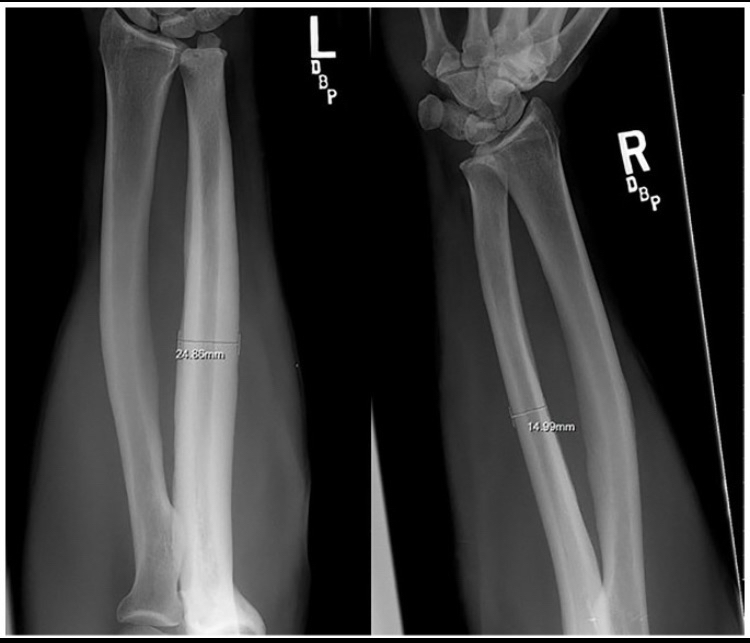

Many of you may already know about bareback rodeo, a sport that requires the rider to have their forearm directly strike the hip bone. Here is a literal excerpt from the study describing what happens: “On observing a contestant who is riding, the riding arm is noted to contact the anterior iliac crest and the heavily resined chaps (Fig. 3). The event requires strength, timing, balance, and courage. Ideally, the forearm should be tucked against the pelvis and chaps. Failure to maintain this position results in a hammering action of the forearm against the pelvis and chaps.“You don’t have to be particularly smart to understand this literally; the scientists stated that the hypertrophy that occurs is the result of direct impact or a “hammering action.”If you’re wondering about the extent of the bone growth, to be frank there was massive hypertrophy, although it varied among participants (I will explain the reasons for this variation).In one sample, the diameter of the ulna increased by 92% and the bone’s cross-sectional area by 262%, which are extremely large biological increases, especially considering participation in this sport is prohibited before age 18.Some might argue that this hypertrophy is due to muscle tension rather than direct impact on the bone, but this is incorrect for several reasons.First, many sports apply intense torsion forces to bones but do not cause even a 10% increase as observed in rodeo riders.Second, the hypertrophy occurs exclusively at the area where the ulna contacts the hip.Third, the hypertrophy was observed only in riders who did not use a saddle; the saddle acts as a barrier preventing friction and impact with the hip bone, and its absence allows direct friction and impact.Fourth, the variation in hypertrophy among participants is likely because some wore protective gear to prevent friction while others did not (see figure 2 to view the bone hypertrophy) [25].

(Figure 2, an image showing bone hypertrophy, please note that the increase in diameter here was approximately 62%, but the largest increase reached 92%)